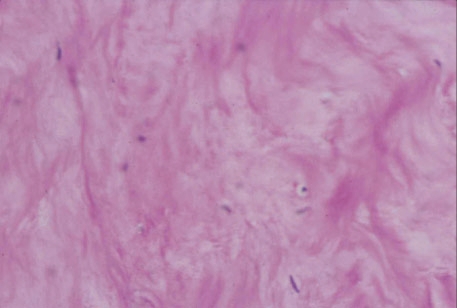

tendão saudável - observem como as fibras estão paralelas

(REES et al  - 2006)

tendinite avançada (cadê as fibras em paralelo?)

REES et al (2006)